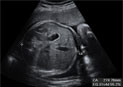

Ecografía 4D de un feto gesticulando en el tercer trimestre de embarazo

La vitalidad de este bebé es notoria: mueve manos y brazos con gran soltura y gesticula con la cara. Se aprecia claramente el movimiento de brazos y manos, que se abren y cierran acercándose o separándose del rostro del pequeño.